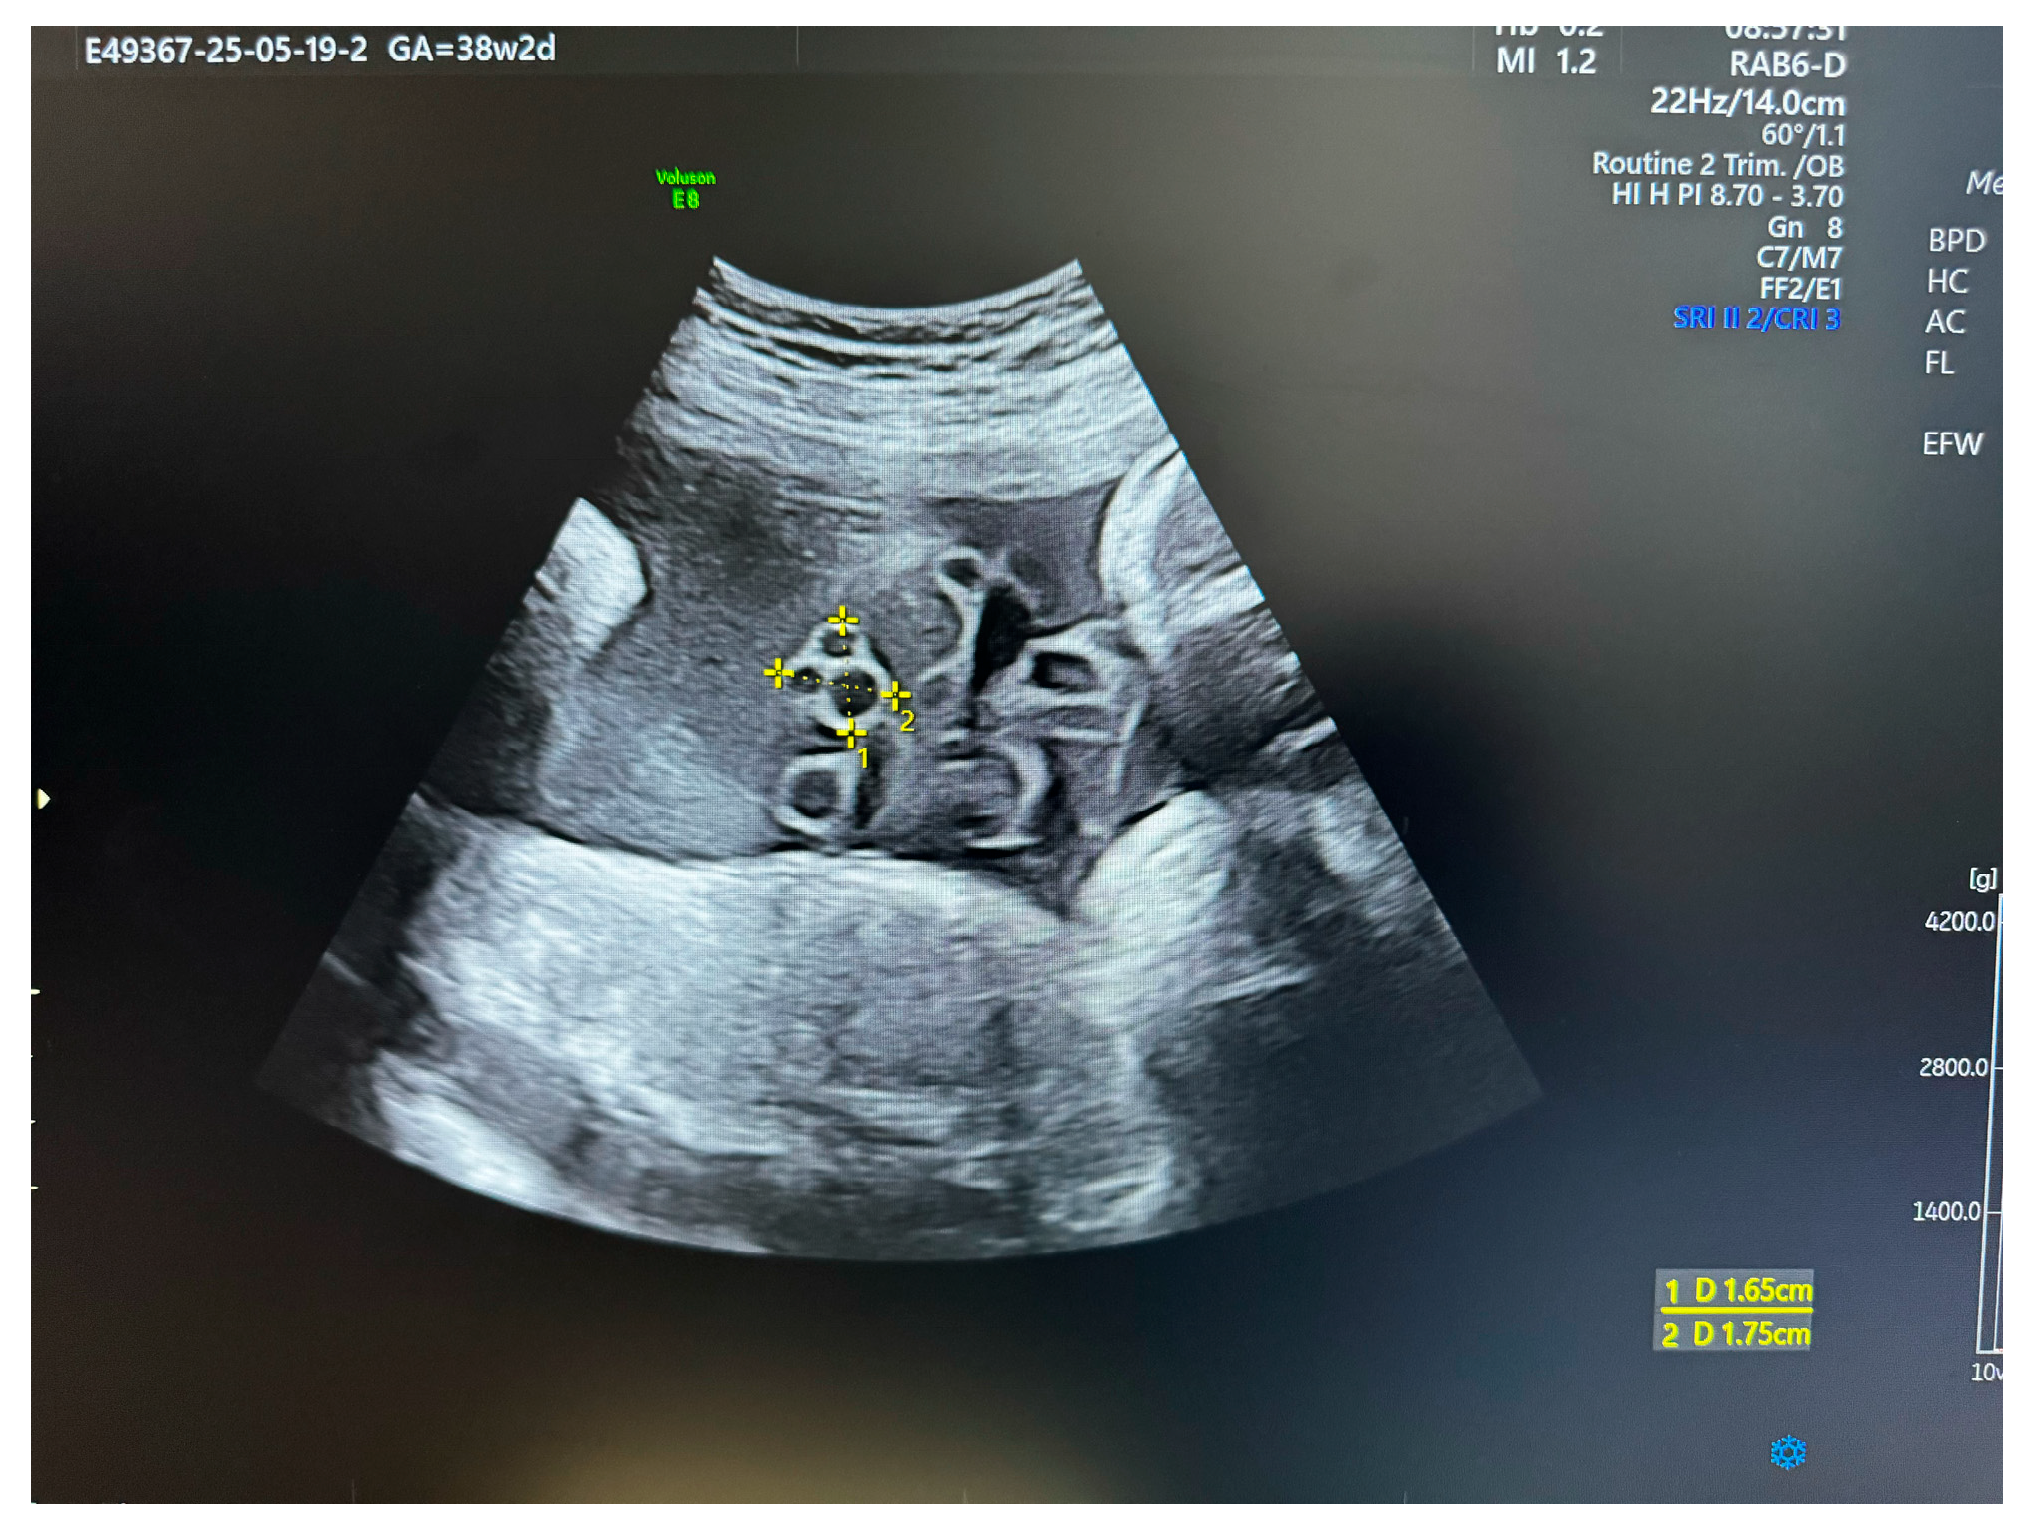

Figure 2.

US section image of a normal umbilical cord at 38 weeks of gestation.

Measuring Wharton’s Jelly Area

The cross-sectional area of Wharton’s jelly can be measured sonographically. This is achieved by obtaining a clear transverse view of a free loop of the cord, measuring the total cross-sectional area of the cord, and then subtracting the measured cross-sectional areas of the two arteries and the vein [2,35]. To aid in the interpretation of these measurements, several studies have published nomograms and reference curves that chart the normal trajectory of WJ area expansion across gestation. These data consistently show a linear increase in the WJ area during the first and second trimesters, which then begins to plateau at approximately 32 weeks’ gestation [2,35]. These nomograms allow for the objective classification of a cord as having a reduced or excessive amount of WJ relative to gestational age norms.